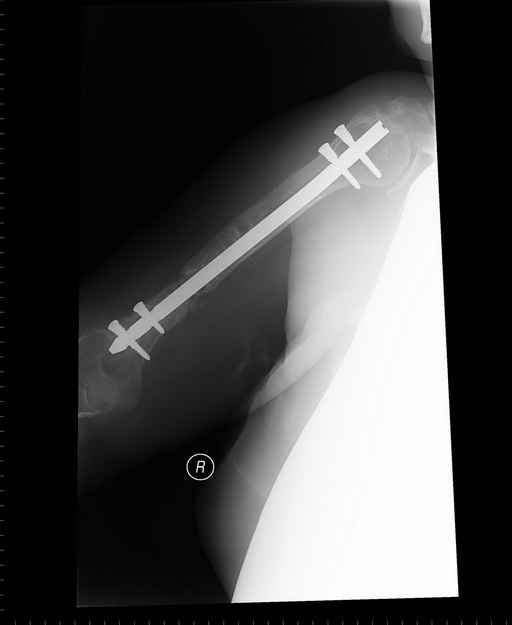

Больная 48 лет, медсестра-массажист, перелом плеча 7 лет назад, оперирована 4-кратно и безуспешно

Больная 48 лет, медсестра. Травма получена 7 лет назад, оперирована первично в Турции - остеосинтез пластиной - несращение - реостеосинтез стержнем там же через год (обычным, с выстоянеием его в полость плеча) - несращение - поступила к нам впервые в марте 2008 года - удаление стержня, реостеосинтез пластиной и костная пластика, в течение 2 лет лизис кости вокруг винтов, смещение фиксатора, в марте 2010 - удаление пластины, реостеосинтез интрамедуллярным стержнем с блокированием (рассверливание + костная пластика). В динамике - вновь лизис в области перелома, нестабильность дистальных блокирующих винтов.

Клинически фиксация пока действительно стабильна, но на рентгенограммах резорбция кости в области дистальных блокирующих винтов и миграция одного из них.